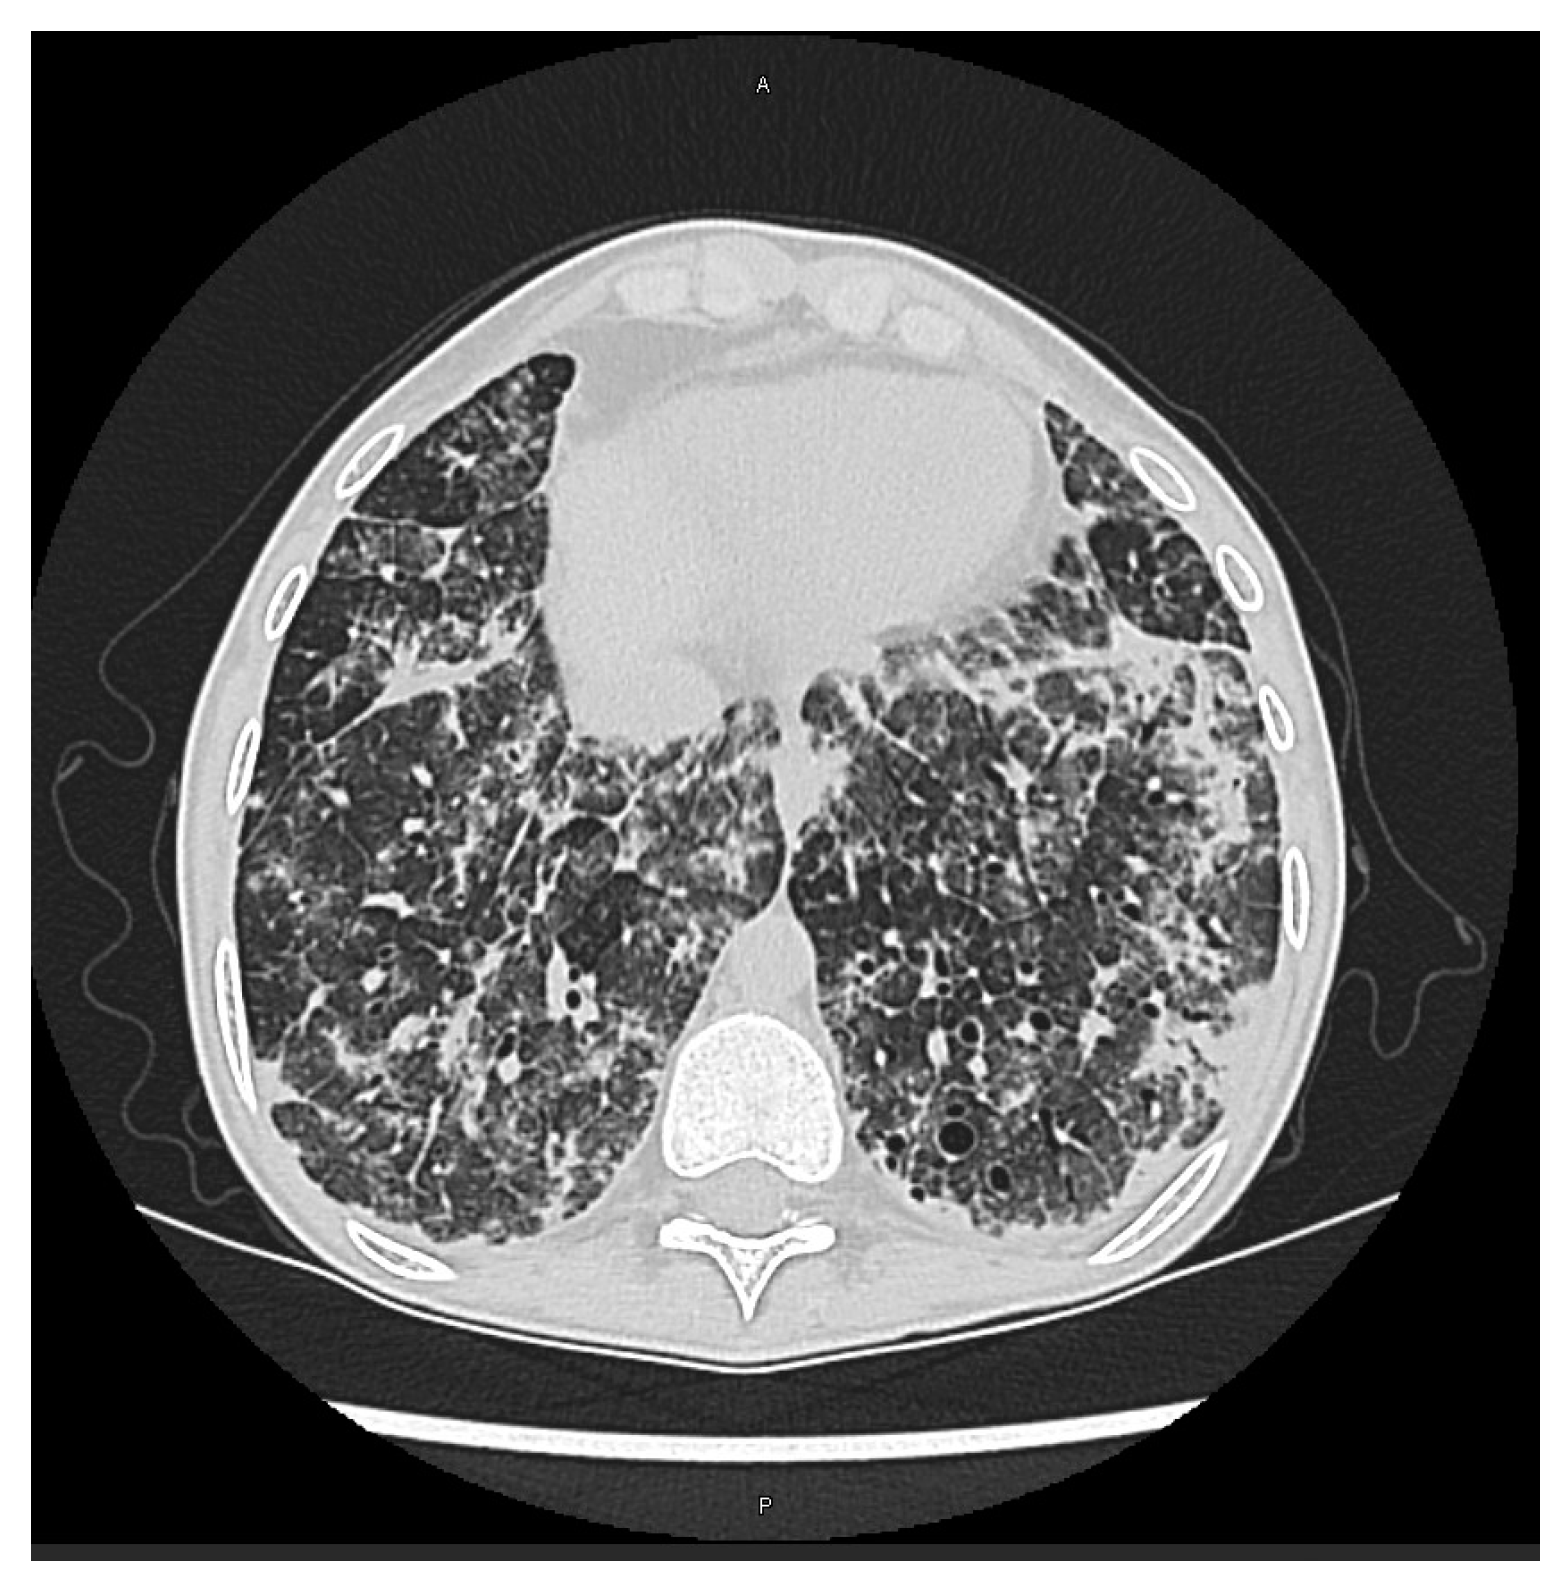

- CMV pneumonitis: Detection of CMV by QNAT in bronchoalveolar lavage (BAL) fluid reflects CMV replication in the lung and the increase in DNA levels correlates with symptomatic CMV disease [33]; qualitative detection of CMV DNA in BAL is not specific for CMV pneumonitis diagnosis [34]. When clinically feasible, TBLB can distinguish CMV pneumonitis from acute rejection; a definitive diagnosis is made when CMV inclusion bodies are present in biopsies and/or CMV viral antigens are found during immunohistochemistry or DNA hybridization tests are positive on lung tissue biopsies [33]. In the case of the impossibility to obtain allograft lung tissue, a presumptive diagnosis of CMV pneumonitis can be based, in an appropriate clinical and radiological setting, on the detection of virus with QNAT or CMV culture in BAL fluid [33], nevertheless, it should be noted that this approach cannot differentiate viral shedding from tissue-invasive disease.